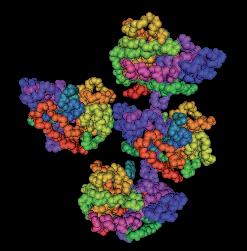

Immagine al microscopio di cellule leucemiche. Le sfere rosse del pacmen rappresentano gli enzimi collagenasi.

Questo vale anche per le cellule leucemiche. Una caratteristica di questa forma di tumore del sangue è l’eccesso di produzione di globuli bianchi, i pazienti affetti da leucemia muoiono principalmente, perché queste cellule bloccano la circolazione del sangue. In molti casi i leucemici muoiono per il cedimento di vari organi, in particolare ‘gli organi filtro’: il fegato e la milza. Milioni di globuli bianchi invadono questi organi attraverso il flusso sanguigno. Queste cellule cancerose producono immense quantità di enzimi che digeriscono il collagene, digerendo letteralmente questi organi dall'interno.

La foto nella pagina a fianco mostra una sezione trasversale al microscopio del fegato di un paziente con ‘leucemia linfatica’. Ciascuno dei piccoli puntini viola nella foto è un globulo bianco (in questo caso linfocita) che ha invaso il tessuto del fegato (aree rosa).

Considerando l’enorme quantità di questi puntini viola e il numero di enzimi che assimilano il collagene che ciascuno produce, è facile prevedere l’ingente distruzione del tessuto connettivo e il danno apportato all’organo da questo tipo di cancro.

La leucemia è un buon esempio di come la comprensione dei meccanismi delle cellule tumorali, la produzione di enzimi che digeriscono il collagene da parte dei globuli bianchi, per poter studiare terapie efficaci.

Immagine al microscopio della leucemia linfatica

Globuli bianchi affetti di cancro (linfociti) invadono il fegato L’enorme quantità di collagenasi prodotte da queste cellule distruggono l’organo e causano insufficienza epatica.